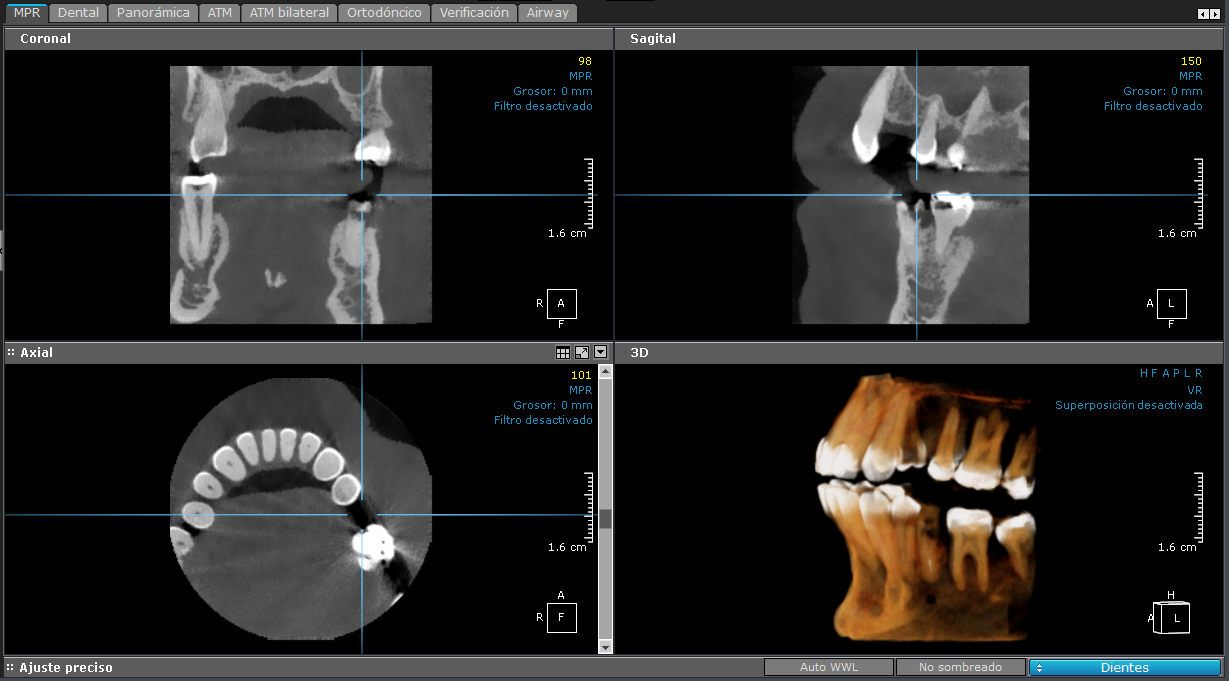

3D - Maxilar Superior

maxilar superior

Esta imagen está centrada en el maxilar superior.